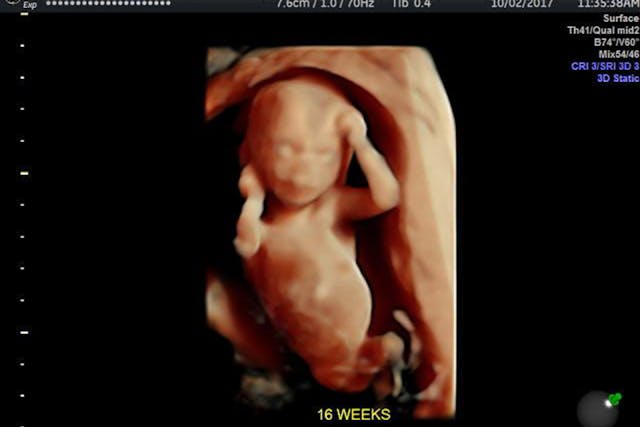

… [A] growing body of scientific research demonstrates that fetal CNS maturation is not required for pain perception. In 2016 the Journal of Pain Research published a summary of multiple different scientific studies all leading to the conclusion that “an early form of pain may appear from the 15th week of gestation onward.” This early physiologic response “is different than emotional pain felt by the more mature fetus,” but it is still a form of physical pain.

Pierucci is correct. A 2002 study, titled, “Anaesthesia for fetal surgery,” shows that for varying types of fetal surgery, beginning at 18 weeks gestation, children in utero are routinely administered anesthesia. The Charlotte Lozier Institute notes this as well, stating in their well-sourced fact sheet on fetal pain that, according to at least four cited studies, “Perinatal medicine now treats unborn babies as young as 16 weeks post-fertilization (18 weeks gestation). Pain medication for unborn patients is routinely administered as standard medical practice.” Lozier also points out that “[t]he leading textbook on clinical anesthesia says: ‘It is clear that the fetus is capable of mounting a physiochemical stress response to noxious stimuli as early as 18 weeks gestation (16 weeks post-fertilization).'”